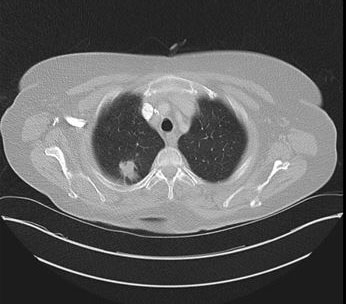

Case Report: We report the case of a 74-year-old patient with giant hiatal hernia. He presented with sub-acute symptoms (e.g., vomiting, appetite loss, and hematemesis). Considering the symptomatology and complementary tests, we decided to perform a laparoscopic hernia repair using mesh reinforcement. We provided a commented operative video to describe the surgical procedure. We then discussed the surgical technique and decided how to conduct a safe and efficient repair.